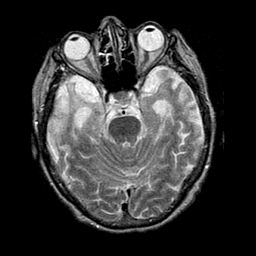

Pick's Disease, MR Study mr-t2 -- Slice #7

[Home][Help][Clinical] Slice 7